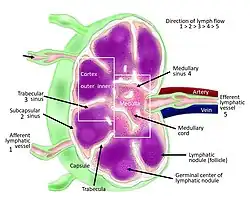

Each lymph node is surrounded by a fibrous capsule (made of collagenous connective tissue),[3] which extends inside a lymph node to form trabeculae.[4] The substance of a lymph node is divided into the outer cortex and the inner medulla.[4] These are rich with cells.[5] The hilum is an indent on the concave surface of the lymph node where lymphatic vessels leave and blood vessels enter and leave.[5]

Lymph enters the convex side of a lymph node through multiple afferent lymphatic vessels, and from there, it flows into a series of sinuses. Upon entering the lymph node, lymph first passes into a space beneath the capsule known as the subcapsular sinus, then moves into the cortical sinuses. After traversing the cortex, lymph collects in the medullary sinuses. Finally, all of these sinuses drain into the efferent lymphatic vessels, which carry the lymph away from the node, exiting at the hilum on the concave side.

Subdivisions

A lymph node is divided into compartments called nodules (or lobules), each consisting of a region of cortex with combined follicle B cells, a paracortex of T cells, and a part of the nodule in the medulla.[17] The substance of a lymph node is divided into the outer cortex and the inner medulla.[4] The cortex of a lymph node is the outer portion of the node, underneath the capsule and the subcapsular sinus.[17] It has an outer part and a deeper part known as the paracortex.[17] The outer cortex consists of groups of mainly inactivated B cells called follicles.[5] When activated, these may develop into what is called a germinal center.[5] The deeper paracortex mainly consists of the T cells.[5] Here the T-cells mainly interact with dendritic cells, and the reticular network is dense.[18]

The medulla contains large blood vessels, sinuses and medullary cords that contain antibody-secreting plasma cells. There are fewer cells in the medulla.[5]

Lymph flow

Lymph enters the convex side of a lymph node through multiple afferent lymphatic vessels, which form a network of lymphatic vessels (Latin: plexus) and flows into a space (Latin: sinus) underneath the capsule called the subcapsular sinus.[5][4] From here, lymph flows into sinuses within the cortex.[4] After passing through the cortex, lymph then collects in medullary sinuses.[4] All of these sinuses drain into the efferent lymphatic vessels to exit the node at the hilum on the concave side.[4]

These are channels within the node lined by endothelial cells along with fibroblastic reticular cells, allowing for the smooth flow of lymph. The endothelium of the subcapsular sinus is continuous with that of the afferent lymph vessel and also with that of the similar sinuses flanking the trabeculae and within the cortex. These vessels are smaller and do not allow the passage of macrophages so that they remain contained to function within a lymph node. In the course of the lymph, lymphocytes may be activated as part of the adaptive immune response.

There is usually only one efferent vessel though sometimes there may be two, in contrast to the multiple afferent channels that bring lymph into the node.[22] Medullary sinuses contain histiocytes (immobile macrophages) and reticular cells, the former of which, along with T and B cells, become activated in the presence of antigens through lymphatic flow. The fewer efferent vessels allow this flow to be slowed, providing time to activate and distribute a larger number of immune cells in the event of an infection.

A lymph node contains lymphoid tissue, i.e., a meshwork or fibers called reticulum with white blood cells enmeshed in it. The regions where there are few cells within the meshwork are known as lymph sinus. It is lined by reticular cells, fibroblasts and fixed macrophages.[23]